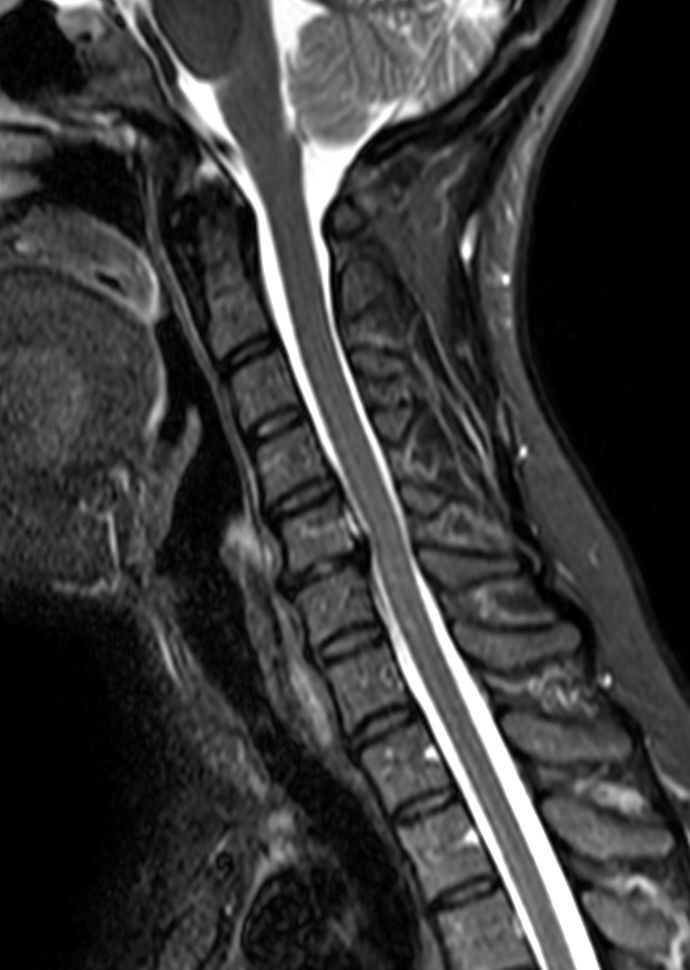

Sagittal STIR TSE

Sagittal T2w TSE mDIXON XDIn phase

Sagittal T2w TSE mDIXON XDPartial FatSat

Sagittal T2w TSE mDIXON XDWater only